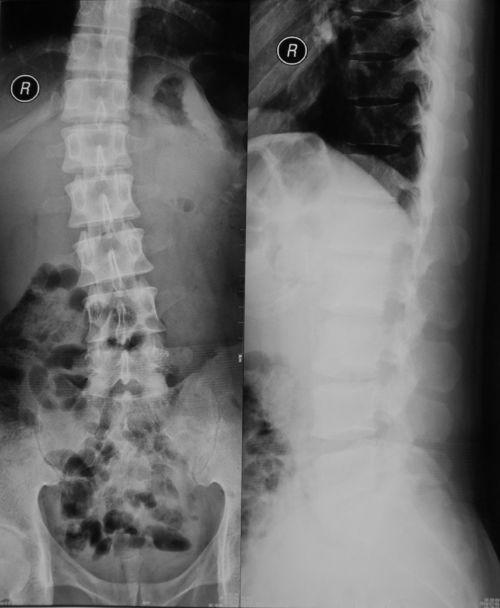

首先,得先了解这腰椎间盘突出究竟是个啥。简单来说,它就是腰椎间盘的纤维环破裂,导致髓核突出,压迫神经根,引起腰痛、下肢放射痛等症状。那么,它又是怎么来的呢?常见的原因有: